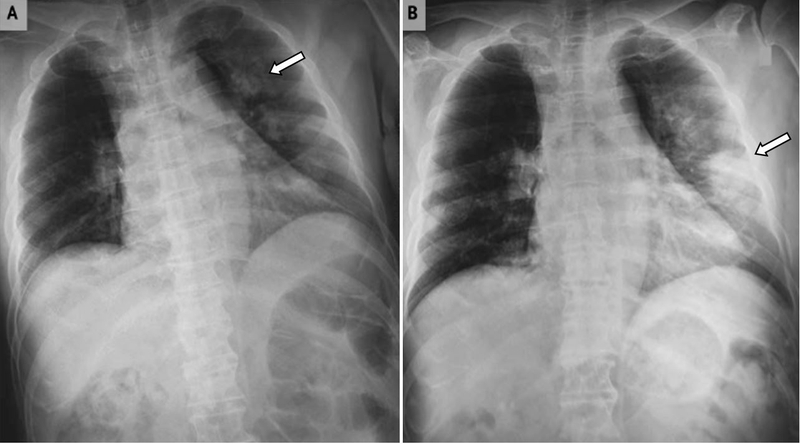

Tác động của vi rút corona đã khiến các tế bào phổi bị tổn thương, gây ra hiện tượng phổi xơ trắng xóa khi chụp X - quang và khiến nhiều người không khỏi lo lắng. Theo nhiều nghiên cứu trên thế giới thì tình trạng phổi trắng hậu Covid có rất nhiều nguyên nhân, trong đó sự phá hủy của vi rút chính là nguyên nhân chính, ngoài ra vẫn còn một số nguyên nhân khác.

Hình ảnh phổi trắng xóa hậu Covid